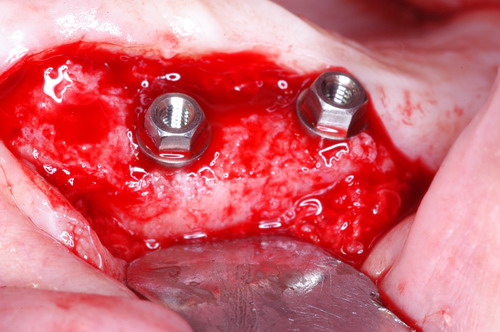

EL USO DEL ARCO GÓTICO DE GYSI , MEDIANTE UNA BÓVEDA PALATINA Y UN APOYO CENTRAL ÚNICO (BO PA YA CU) , EN LA UBICACIÓN DE LA RELACIÓN CÉNTRICA EN UN CASO DE GRAN LAXITUD TENDINOSA CAPSULAR. EL PACIENTE SE PRESENTA A CONSULTA CON UNA EDENTACIÓN PARCIAL, Y GRADO DE MOVILIDAD EXTREMO EN TODAS SUS PIEZAS REMANENTES. SE ESTUDIA EL CASO RADIOGRÁFICA Y CLÍNICAMENTE , Y EL PACIENTE RELATA ESTAR EN ESE ESTADO DESDE HACE MUCHO AÑOS. AL MANIPULAR LA MANDÍBULA EN UN INTENTO DE CONOCER EL ESTADO MUSCULAR DEL SISTEMA, SE OBSERVA UNA GRAN LABILIDAD TENDINOSA CAPSULAR QUE SE MANIFIESTA EN UNA HIPER LAXITUD EN LOS MOVIMIENTOS MANUALMENTE INDUCIDOS DE AMBOS CÓNDILOS DENTRO DE LA CAVIDAD. SE TOMAN IMPRESIONES Y SE MONTA EN UN ARTICULADOR SEMI AJUSTABLE , CORTANDO EN EL YESO LAS PIEZAS QUE SERÁN EXTIRPADAS , CONSERVANDO UNICAMENTE , AMBOS PRIMEROS PREMOLARES INFERIORES , QUE SERÁN UTILIZADOS PARA RETENER MEDIANTE RETENEDORES ELÁSTICOS LA PRÓTESIS INFERIOR , EN LA PRESUNCIÓN DE LA HIPERMOVILIDAD A QUE SERÁ SOMETIDA DADO QUE EN LA GRAN REABSORCIÓN ÓSEA , ES FRECUENTE EL ACERCAMIENTO DE TODAS LAS INSERCIONES MUSCULARES A LA PORCIÓN SUPERIOR DEL REBORDE ÓSEO , LO QUE ATENTARÁ CONTRA LA ESTABILIDAD DE DICHA PRÓTESIS PROVISIONAL. EN UNA PRIMERA SESIÓN CLÍNICO QUIRÚRGICA , SE EXODONCIA TODO EL SECTOR INCISIVO Y CANINO INFERIOR , Y AL OBSERVAR EL REMANENTE ÓSEO CANINO DE AMBOS LADOS , SE IMPLANTA EN FORMA INMEDIATA . TANSCURRIDOS DOS MESES , DONDE LA CICATRIZACIÓN ES ADECUADA , Y LA DINÁMICA MANDIBULAR ACEPTABLE , SE PROCEDE A LA ETAPA QUIRÚRGICA IMPLANTARIA MEDIANTE IMPLANTES SEMI SUMERGIDOS, CON ALGUNAS ZONAS DE REGENERCIÓN ÓSEA GUIADA FIG17 FIG18 FIG19 FIG26 DURANTE LA ETAPA DE CICATRIZACIÓN DE ESTE NUEVO ABORDAJE QUIRÚRGICO , SE ENDODONCIAN AMBOS PREMOLARES INFERIORES CONSERVADOS , LOS QUE EN UN FUTURO , CUANDO YA NO SIRVAN PARA RETENER LA PRÓTESIS REMOVIBLE PROVISORIA INFERIOR , SERÁN CORTADOS COMO RESERVA DE CAPITAL ÓSEO O BIEN COMO ELEMENTO RETENEDOR ANTE CUALQUIER TIPO DE INCIDENCIA IMPLANTARIA. ABORDAMOS LA ETAPA PRIMARIA PROTÉTICA , UNA VEZ TRANSCURRIDOS TRES MESES, MEDIANTE LA UTILIZACIÓN DE CUBETAS INDIVIDUALES , A LAS QUE REALIZAMOS UN RECORTE MUSCULAR EN BASE A STENS VERDE , COMO SI DE UNA PRÓTESIS COMPLETA SE TRATARA. DE ESE MONTAJE OBTENEMOS DOS RODETES DE METACRILATO , PERFECTAMENTE ADAPTADOS A LOS MODELOS FUNCIONALES , A LOS QUE LES OTORGAMOS LA PLANIMETRÍA DERIVADA DEL PARALELISMO CON EL PLANO DE FRANKFURT , Y UNA ALTURA (DV) QUE RESULTA DE LOS MÉTODOS MÉTRICOS DE DIMENSIÓN VERTICAL… Y QUE NOS SERVIRAN ADEMÁS DE TOMAR UNA NUEVA IMPRESIÓN FUNCIONAL MEDIANTE RECORTE MUSCULAR , PARA ADAPTAR UN DISPOSITIVO CONSISENTE EN UNA BÓVEDA PALATINA SUPERIOR , Y UN TORNILLO CENTRAL INFERIOR , LOS QUE DESPUÉS DE UN ENTRENAMIENTO ADECUADO DEL ENFERMO , NOS PERMITIRÁ REPRODUCIR EN EL BÓVEDA , EL ARCO GÓTICO DE GYSI , ENCONTRANDO DE ESTA MANERA LA OCLUSIÓN EN RELACIÓN CÉNTRICA. ACTUALMENTE ESTE MÉTODO HA SIDO RECREADO MEDIANTE LA DENOMINACIÓN DE: FIG50 FIG51 FIG52 OBTENIDO EL DIBUJO DEL ARCO GÓTICO , INSINUAMOS EN EL VÉRTICE DEL MISMO UNA PERFORACIÓN QUE FIJARÁ LA PUNTA DEL TORNILLO EN ESA POSICIÓN: RELACIÓN CÉNTICA FIG55 FIG56 FIG57 CON ESTOS PARÁMETROS SE CONSTRUYEN DOS SOBREDENTADURAS ABROCHADAS EN RÓTULAS SUPRA IMPLANTES , QUE LE OTORGAN FIJACIÓN SUFICIENTE , DANDO A LA OCLUSIÓN TODOS LOS ELEMENTOS DE UNA: OCLUSIÓN MUTUAMENTE COMPARTIDA, REFERENCIA II CON UN ESQUEMA OCLUSAL DE : FUNCIÓN DE GRUPO BILATERAL POSTERIOR DE ACCIÓN CANINA DESPUÉS DE LAS REVISIONES PERTINENTES A LA SEMANA , EL MES Y LOS SEIS MESES DE TERMINADA LA REHABILITACIÓN , SE CITA AL ENFERMO PARA UN NUEVO CONTROL AL AÑO Y MEDIO Y SE OBSERVA UNA PERFECTA SITUACIÓN TISULAR , CLINICA Y RADIOGRAFICAMENTE CONTROLADA , Y ADEMÁS LA PERMANENCIA DEL MISMO ESQUEMA OCLUSAL OTORGADO DESDE EL PRINCIPIO. SE CONTROLA RADIOGRAFICAMENTE Y SE DA EL ALTA DEFINITIVA RECOMENDANDO EL CONTROL DOS VECES AL AÑO. REFERENCIAS: I : II. : III: